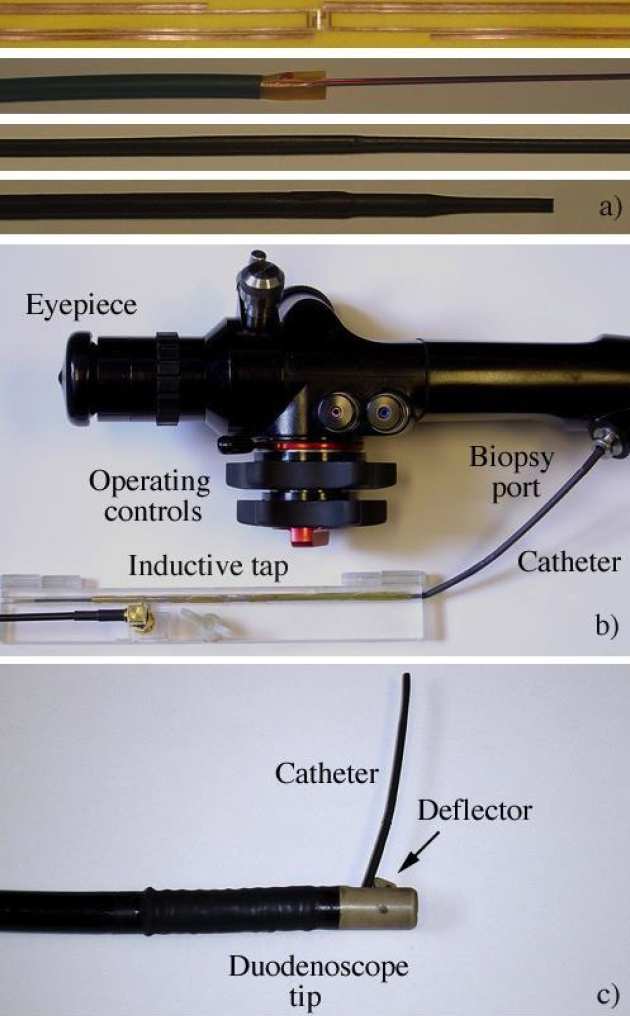

Richard Syms, ian Young, Munir Ahmad, Simon Taylor-Robinson and Marc Rea

We have demonstrated a catheter-based RF receiver for internal magnetic resonance imaging is demonstrated. The device consists of a double-sided thin-film circuit, wrapped around a hollow catheter and sealed in place with heatshrink tubing. Signals are detected using a resonant L-C circuit at the catheter tip, and transmitted along the catheter using an array of coupled L-C circuits arranged as a magneto-inductive waveguide, a form of low frequency metamaterial. Coupling to a conventional RF system is accomplished using a demountable inductive transducer. Protection against external B1 and E fields is obtained by using figure-of-eight elements with an electrical length shorter than that of an immersed dipole. The system is primarily designed for biliary imaging, can pass the biopsy channel of a side-opening duodenoscope and is guidewire-compatible, potentially allowing clinicians to implement MR image guided procedures without changing their standard practice. Decoupling against B1 and E fields has been verified, and in vitro 1H magnetic resonance imaging with sub-mm resolution demonstrated at 1.5 T using phantoms.

|---|

| a) Stages in construction of catheter-based receiver; b) receiver with demountable transducer attached and passing into the biopsy channel of a non-magnetic duodenoscope; c) receiver passing from the side-port. |

|---|

| Axial 1H MR images obtained using a) an 8-element array and b) the catheter receiver; c) high-resolution image obtained using the catheter. |